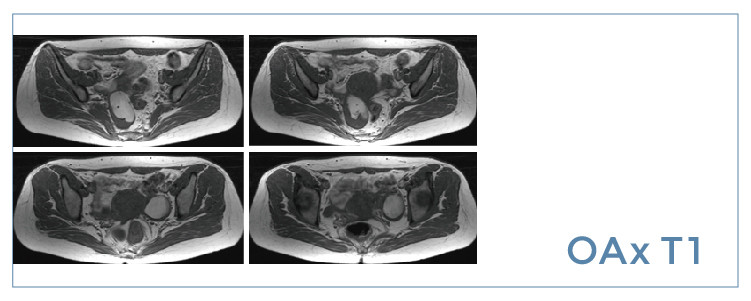

【朗润影像档案】磁共振影像病例分享(编号20190705)